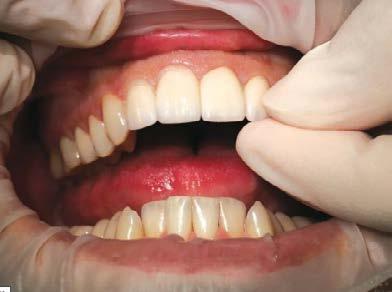

Cita 3. Entrega de las restauraciones finales

Comencé la cita de entrega de las restauraciones finales probando las carillas centrales y después continué trabajando hacia los laterales. Luego de confirmar que el ajuste era preciso, le ofrecí al paciente la oportunidad de mirarse al espejo, los retiré y procedí con la limpieza de la superficie interior de las restauraciones (Figura 11).

Usando un encerado de diagnóstico para presentarle al paciente un moc kup intraoral de la sonrisa propues ta, pudimos trabajar en conjunto y

ponernos de acuerdo en el diseño de la restauración final que lucirá y se sen tirá bien para el paciente (Figura 14).

Las carillas BruxZir Esthetic fueron justo lo que el paciente esperaba y la emoción por su nueva sonrisa era evi dente (Figura 15).